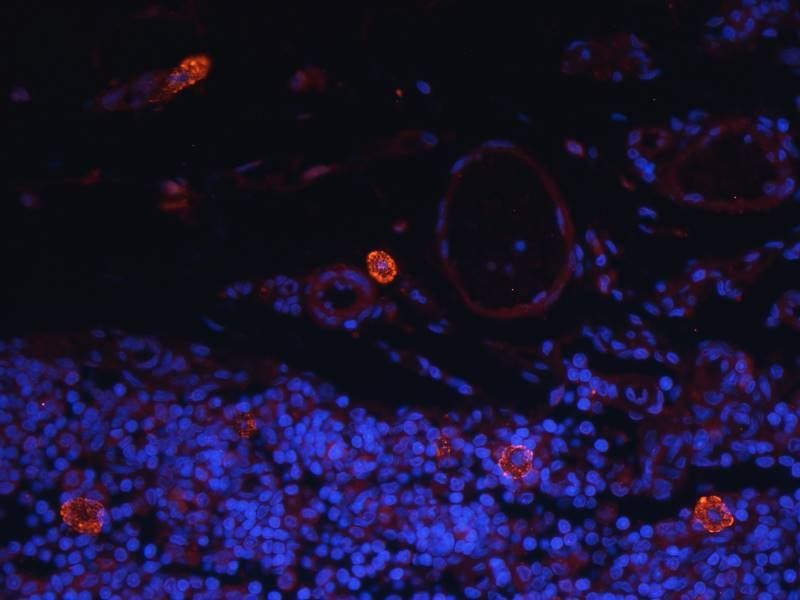

IHC staining of FFPE human brain with Ubiquitin antibody (clone PBQN-1). Required HIER: boil tissue sections in pH9 10mM Tris with 1mM EDTA for 10-20 min followed by cooling at RT for 20 min.